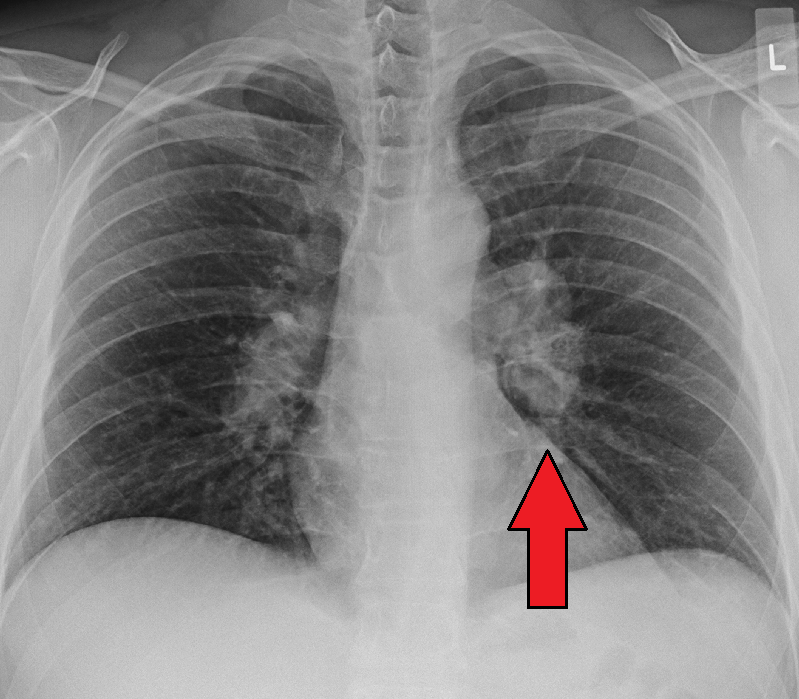

Sarcoidosis is a systemic disease characterized by growing granulomas in various body organs and is more prevalent in African American women.

The granulomas mostly affect the hilar lymph nodes and lungs, causing restrictive lung disease.